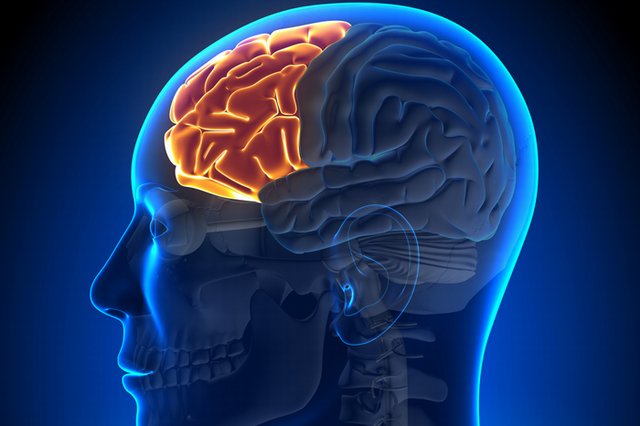

إن إفراز مادة الدوبامين بكثرة من قبل الدماغ أثناء مشاهدة مناظر الجنس، ترهق الدماغ وبخاصة المنطقة الأمامية من الدماغ (الناصية)، حيث هذه المنطقة مهمة في اتخاذ القرار وهي أشبه بالفرامل بالنسبة للسيارة، تصور نفسك تقود سيارة ذات فرامل معطلة، لا شك أن احتمال أن ترتكب حادثاً أمر وارد. هذه المنطقة لها ممرات ترتبط بمنطقة المكافأة في الدماغ وبالتالي تتأثر أثناء مشاهدة أفلام الجنس، وبالنتيجة تتأثر قراراتك وقدرتك على التحكم بنفسك.

تمتد الأضرار إلى منطقة الناصية من الدماغ ومع مرور الزمن تتأذى هذه المنطقة وتتآكل تدرجياً وتفقد القدرة على اتخاذ القرار الصائب.

لقد أثبتت دراسات سابقة أن الإدمان على المخدرات يسبب تلفاً في المنطقة الأمامية للدماغ، وقد لوحظ أن مدمني الخمر والمخدرات يعانون من انكماش المنطقة الأمامية من أدمغتهم مما يفقدهم السيطرة على تصرفاتهم. ولذلك فإن إدمان النظر للنساء المتبرجات سوف يكون له نفس الأثر على الدماغ وربما أكثر، ولكن غالباً الناس لا يدركون حجم هذا الضرر إلا متأخراً.

يعتبر العلماء المنطقة الأمامية من الدماغ أو Frontal Loob مثل المكابح (الفرامل) بالنسبة للسيارة، فعندما يكثر الإنسان من مشاهدة المناظر الجنسية، فإن هذه المنطقة المسؤولة عن القيادة والتحكم تتعب وتتلف أجزاء مهمة منها تماماً مثل تلف فرامل السيارة، فتصبح حالة الإنسان وكأنه يقود سيارة بسرعة هائلة دون توقف ومن دون فرامل... ماذا ستكون حاله؟ بينما في حالة الزواج فإن هذه المنطقة تنشط وتنمو وتساعد الإنسان على الإبداع واتخاذ القرارات السليمة.. والنجاح في الحياة!!